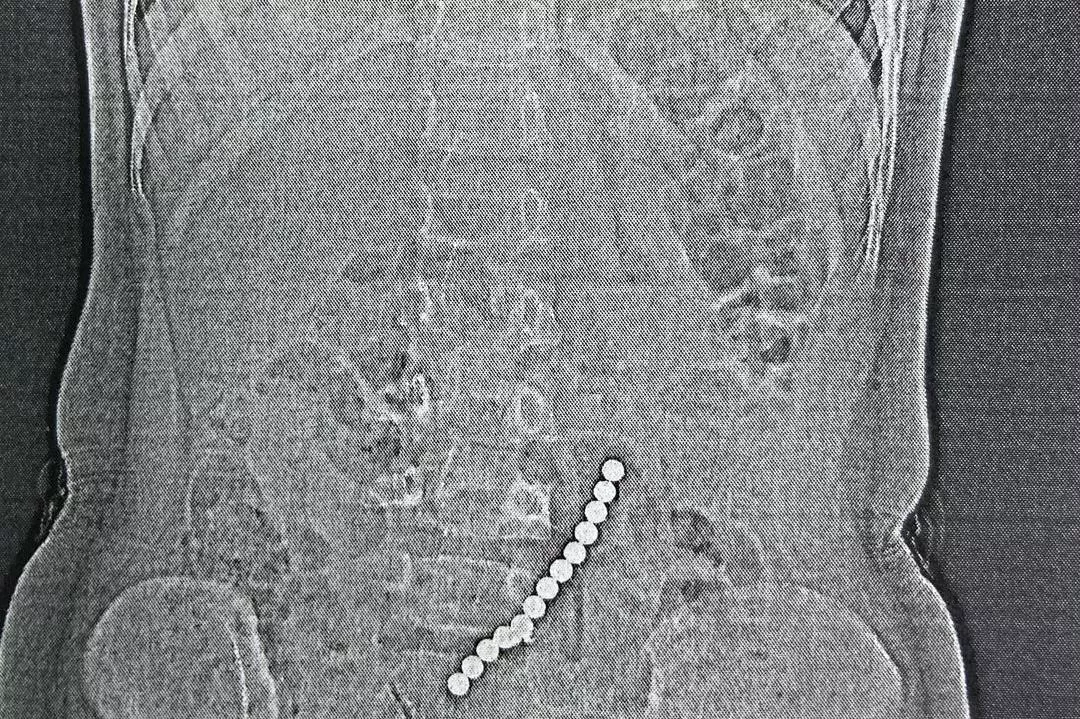

Ребенку выполнили диагностические исследования – рентген, УЗИ и КТ. На снимках врачи увидели единую цепочку из 13 магнитных шариков. Мальчик наблюдался в течение суток. Медики ожидали, что магниты выйдут естественным путем, но контрольное КТ брюшной полости показало, что шарики расположены в том же месте.

Врачи приступили к лапароскопической операции, но ситуация оказалась намного сложнее: часть магнитов располагалась в одной петле кишечника, часть – в другой. Стенки кишок склеились между собой, что привело к образованию межкишечного свища.